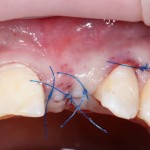

Для надежности можно зафиксировать пинами:

Ну и, швы: